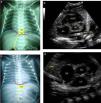

Fig. 1 shows two examples of discordance between assessments of UVC position by anteroposterior chest radiography and the corresponding echocardiographic image. The catheters that were appropriately positioned in the target area were projected into a wide range of vertebral bodies (between T7 and T8 and between T11 and T12), as determined by the echocardiography. The performance of the vertebral level method alone in predicting the UVC position was considered below acceptable, as demonstrated by the area under the ROC curve of 0.66, with 95% CI of 0.57–0.74 (Fig. 2).

Anteroposterior chest X-ray showing the umbilical venous catheter in T9, just above the diaphragm and cavoatrial junction, interpreted as well positioned (a) and corresponding echocardiographic image (b) demonstrating the distal end of the catheter in the left atrium, after crossing the interatrial septum (*). In another newborn, the radiographic image showed the catheter between T9 and T10, below the diaphragm and cavoatrial junction, suggesting it is positioned in the liver (c), but its end was correctly identified in the inferior vena cava junction with the right atrium by the echocardiography (d). LA, left atrium; RA, right atrium; AO aorta; UVC, umbilical venous catheter; RVOT, right ventricular outflow tract.